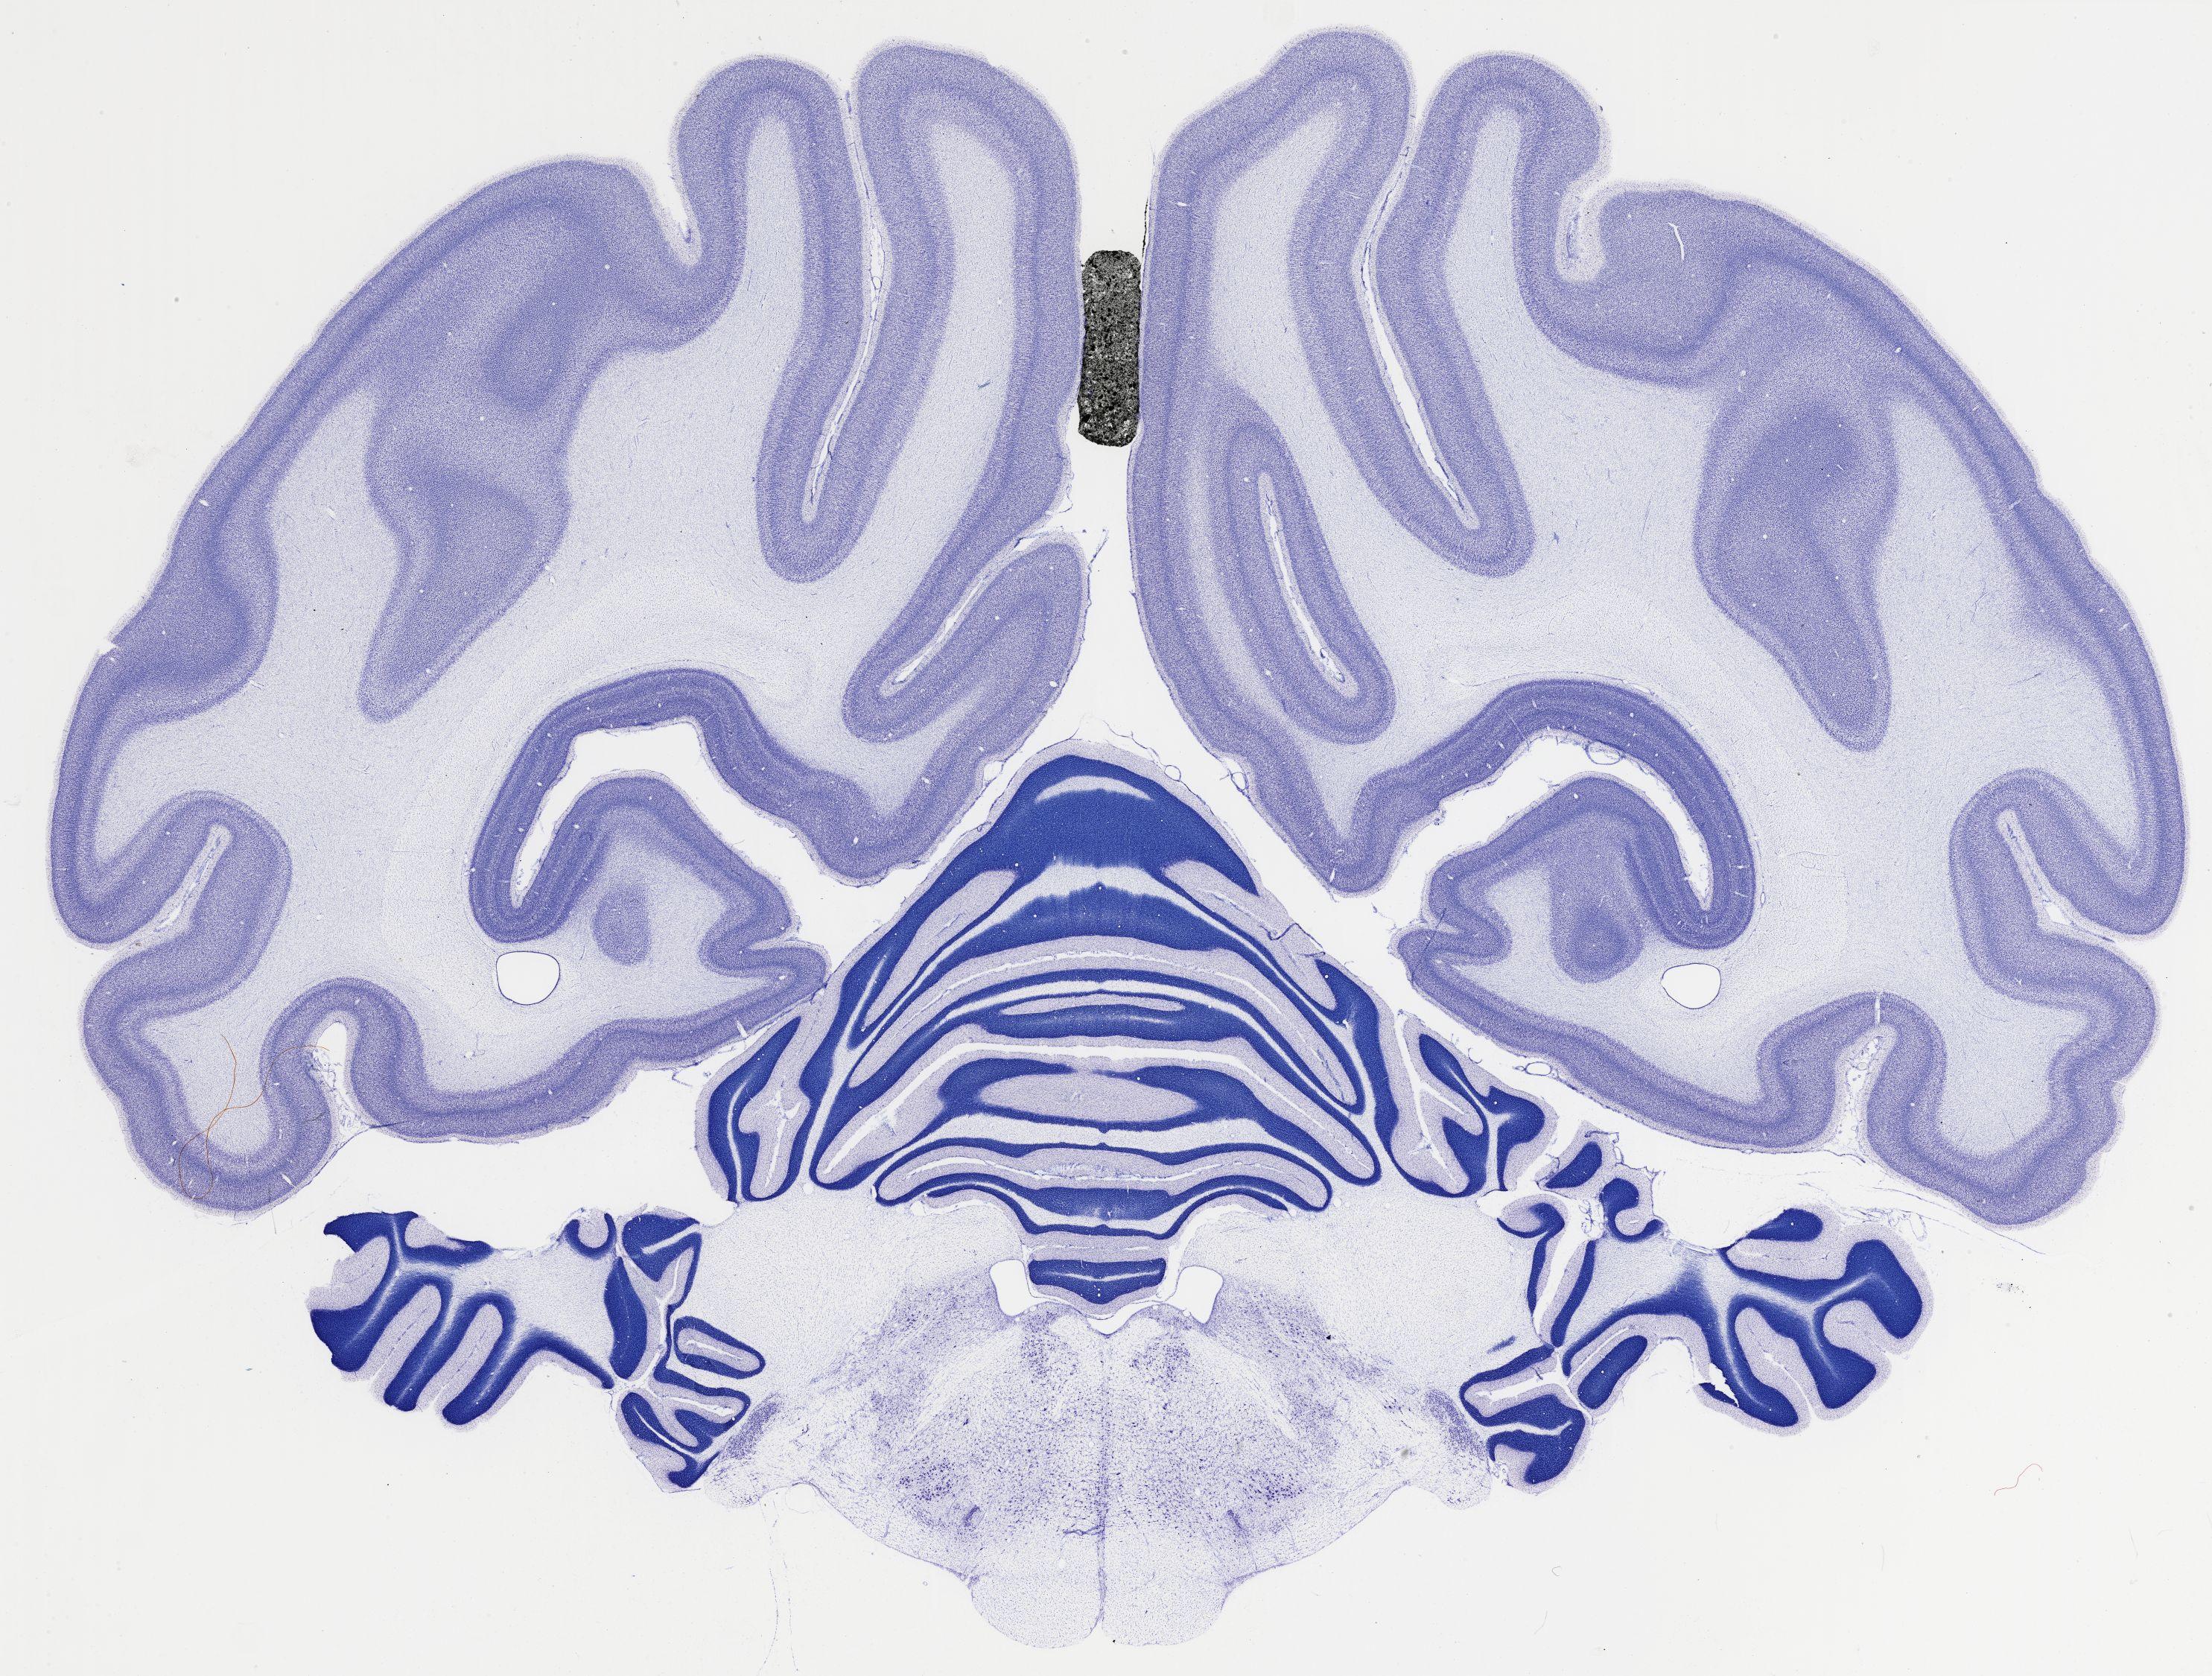

Datasets -> Chlorocebus Aethiops -> Nissl, coronal, histo, Whole-Brain, adult

[ Metadata ]   ·   Source: NeuroScience Associates

thumbnail

524